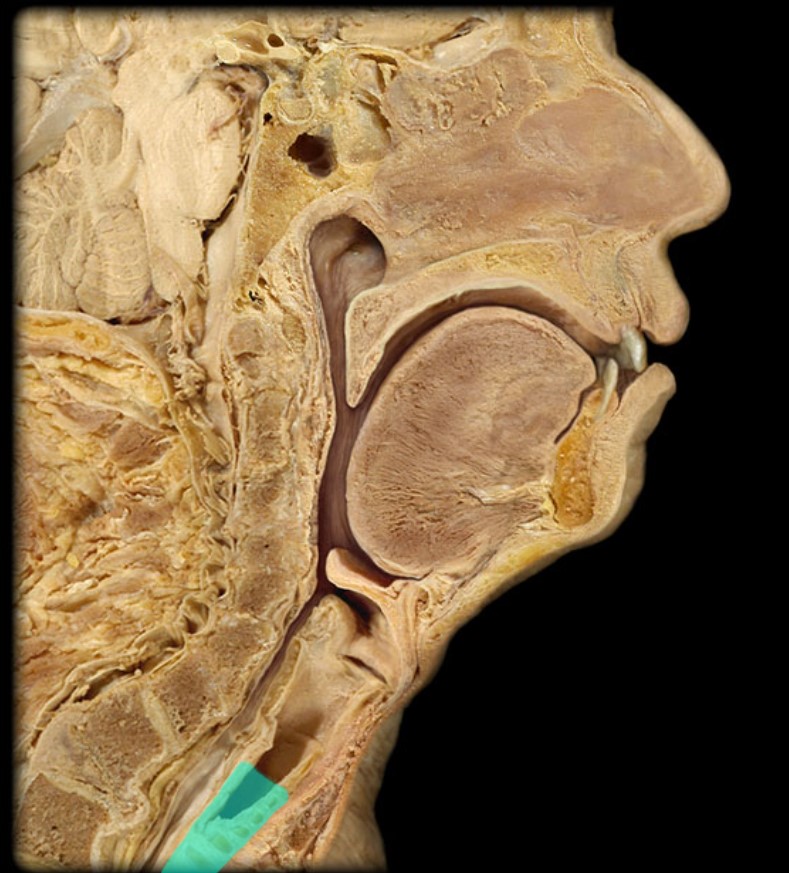

Anatomy 5 - Bifurcated Skull

29 Terms

1

New cards

Thyroid Gland

(Donor Only)

2

New cards

Atlas

3

New cards

Vertebral Artery

(Donor Only)

4

New cards

Nasal Septum

(Donor Only)

5

New cards

Esophagus

6

New cards

Trachea

7

New cards

Vocal Fold

8

New cards

Epiglottis

9

New cards

Hyoid

10

New cards

Mandible

11

New cards

Mylohyoid

12

New cards

Geniohyoid

13

New cards

Genioglossus

14

New cards

Lingual Tonsil

15

New cards

Palatine Tonsil

16

New cards

Uvula

17

New cards

Soft Palate

18

New cards

Palatine Bone

19

New cards

Maxilla

20

New cards

Pharyngeal Tonsil

21

New cards

Auditory Hiatus

22

New cards

Torus Tubarius

23

New cards

Sphenoid Sinus

24

New cards

Inferior Nasal Concha

25

New cards

Middle Nasal Concha

26

New cards

Superior Nasal Concha

27

New cards

Nasal Vestibule

28

New cards

External Nares

29

New cards

Frontal Sinus